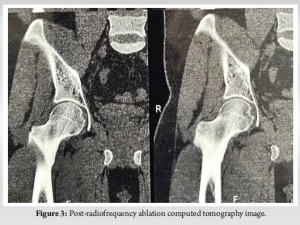

Case Report: We present a case of a 21-year-old male who initially presented with persistent right hip pain. Initial magnetic resonance imaging revealed marrow edema in the right femoral neck with associated joint effusion, leading to a preliminary diagnosis of stress fracture and subsequent misdiagnosis of AVN. The patient’s symptoms persisted despite conservative management. After 6 months of continued symptoms, computed tomography (CT) imaging revealed a characteristic lucent lesion in the inferior cortex of the right femoral neck, confirming the diagnosis of osteoid osteoma. The patient underwent successful radiofrequency ablation (RFA) performed in three cycles.

A 21-year-old male presented with persistent right hip pain that significantly impacted his daily activities. The patient’s initial symptoms began in May 2024, prompting medical evaluation including magnetic resonance imaging (MRI) of the hip. The initial MRI revealed marrow edema in the right femoral neck with associated hip joint effusion and periarticular soft tissue changes. While no definitive signs of AVN were observed, the presence of a stress fracture in the right femoral neck led to the administration of zoledronic acid. Concurrent lumbar spine imaging revealed multiple levels of degenerative changes, including a mild foraminal disc bulge at L3-L4, significant changes at L4-L5 with bilateral nerve compression, and disc protrusion at L5-S1. These findings complicated the clinical picture, potentially contributing to the diagnostic challenge. The patient’s condition progressed, and by July 2024, he experienced worsening hip pain with reduced range of motion. Based on the clinical presentation and previous imaging findings, he was diagnosed with AVN and a femoral stress fracture, leading to a conservative treatment approach with analgesics for 10 days. In October 2024, the presence of a vascular valley was noted, and the patient was advised on lifestyle modifications and dietary changes. Due to persistent symptoms, a repeat MRI was performed in November 2024, which showed mild-to-moderate right hip joint effusion with synovial thickening and subtle marrow edema in the right femoral head, neck, and acetabular roof. Notably, this study did not demonstrate definitive AVN changes, prompting further diagnostic investigation. By December 2024, the patient reported progressive pain radiating from the hip to the right thigh. A computed tomography (CT) scan revealed a critical finding: A characteristic lucent lesion in the inferior cortex of the right femoral neck, consistent with an osteoid osteoma. This discovery led to a definitive change in diagnosis and treatment approach. The patient underwent radiofrequency ablation (RFA) of the osteoid osteoma, performed in three cycles. This case highlights the diagnostic challenges in differentiating between osteoid osteoma and AVN, particularly in young patients presenting with hip pain. The evolution of imaging findings and the importance of maintaining a broad differential diagnosis were crucial in reaching the correct diagnosis. The case also demonstrates the value of advanced imaging techniques, particularly CT scanning, in identifying subtle bone lesions that may be missed on initial MRI studies (Fig. 1-3).